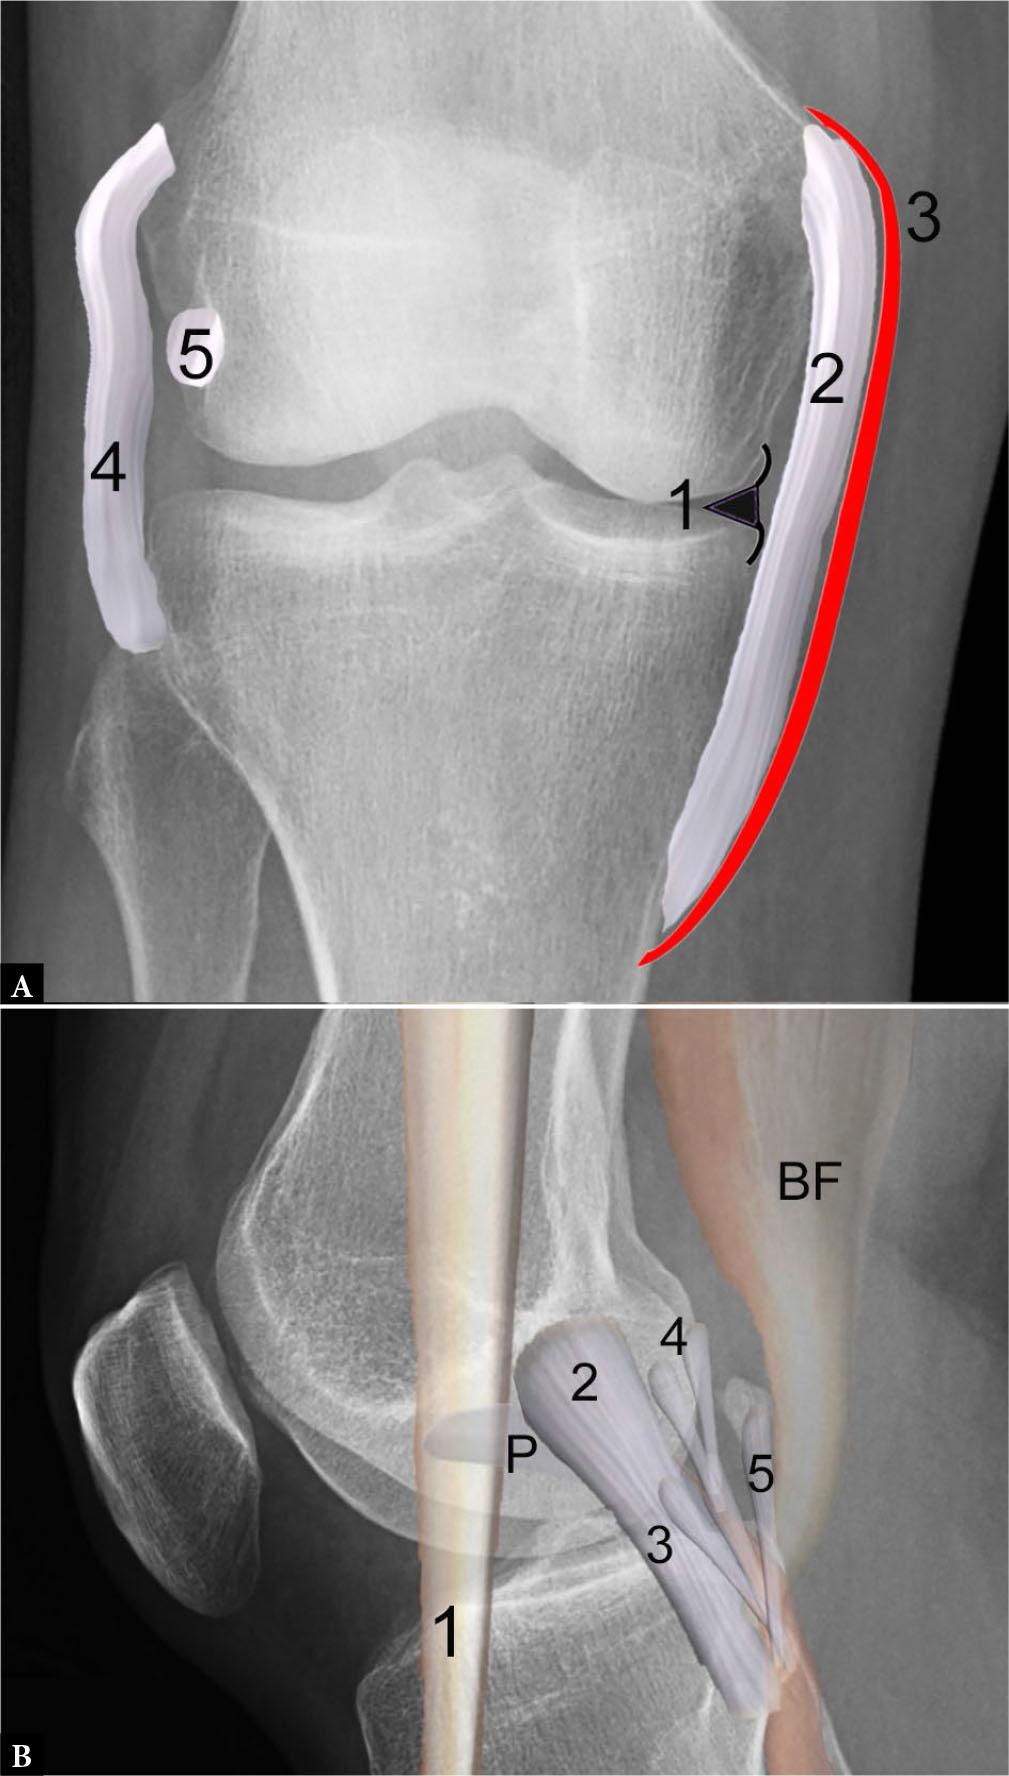

Fig. 9.

Illustrations of medial and lateral supporting structures at the knee joint superimposed on radiographs. A. Illustration of medial collateral ligament (MCL) complex superimposed on PA view of the knee shows the medial meniscal body (1) with deep layer consisting of the attached meniscofemoral and meniscotibial ligaments, middle layer consisting of the tibial collateral ligament (or superficial MCL) (2), with superficial layer composed of crural fascia (3). Note the fibular collateral ligament (4) and popliteus tendon (5) at the lateral knee. B. Illustration of lateral supporting structures, including the iliotibial band (1), fibular collateral ligament (2) running from the femoral condyle to the fibular head and attaching near the biceps femoris (BF) tendon insertion, as well as the posterolateral corner structures consisting of the popliteofibular ligament (3) arising from the fibular styloid and attaching to the popliteus (P) myotendinous junction, the Y-shaped arcuate ligament (4), and the fabellofibular ligament (5)

Additional lateral supporting structures include the popliteus muscle and tendon, biceps femoris tendon, as well as the popliteofibular, arcuate and fabellofibular ligaments (Fig. 9 B). Along with the joint capsule and lateral patellar retinaculum, the lateral gastrocnemius tendon and iliotibial tract provide additional lateral stabilization. MRI allows for a rapid comprehensive assessment of these numerous structures, particularly in the setting of acute multiligamentous injury(30).